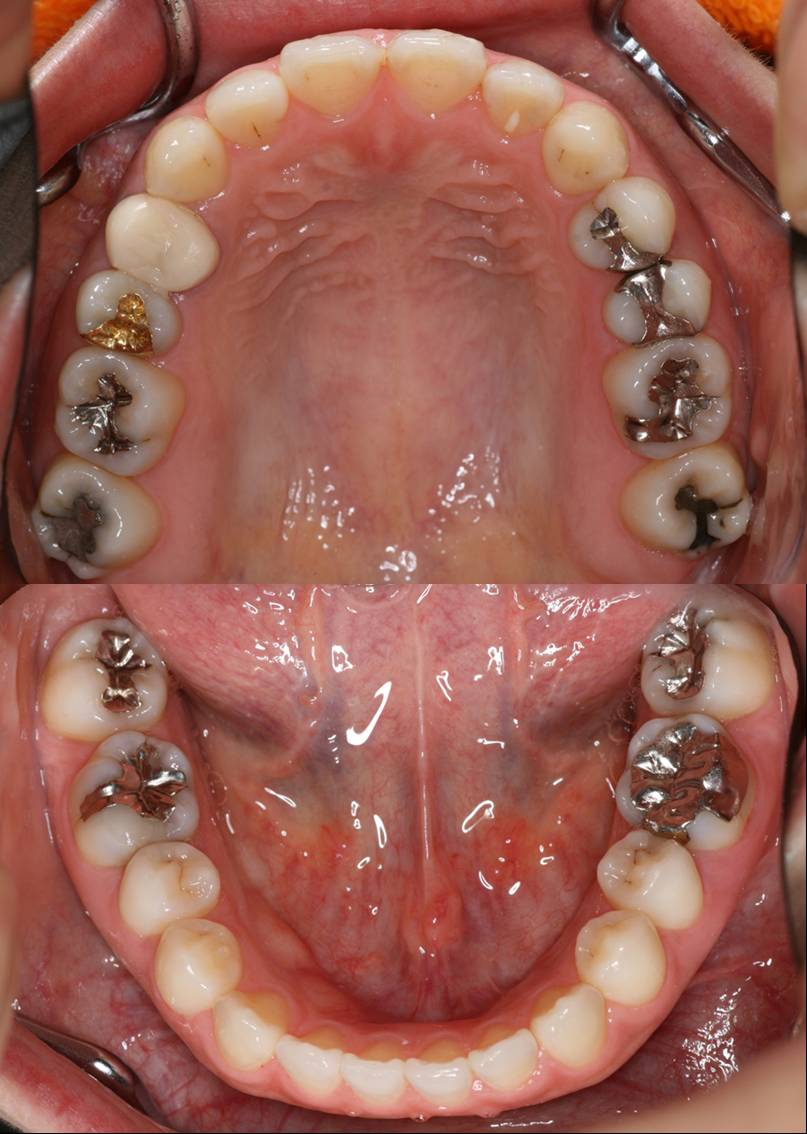

今年ベスト3に確実に入る治療ですから難易度高いです。

さて、何箇所治したでしょう!?(;¬_¬)

レジン  ○本  ゴールド 3本  オールセラミック 1本

答えは、

レジン治療11本でした

長い間お疲れさまでした